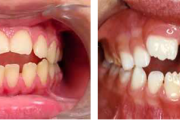

Turritavad ülemised lõikehambad.

Normaalse jäävhammaskonna pilt küljelt ja eest vaadatuna.